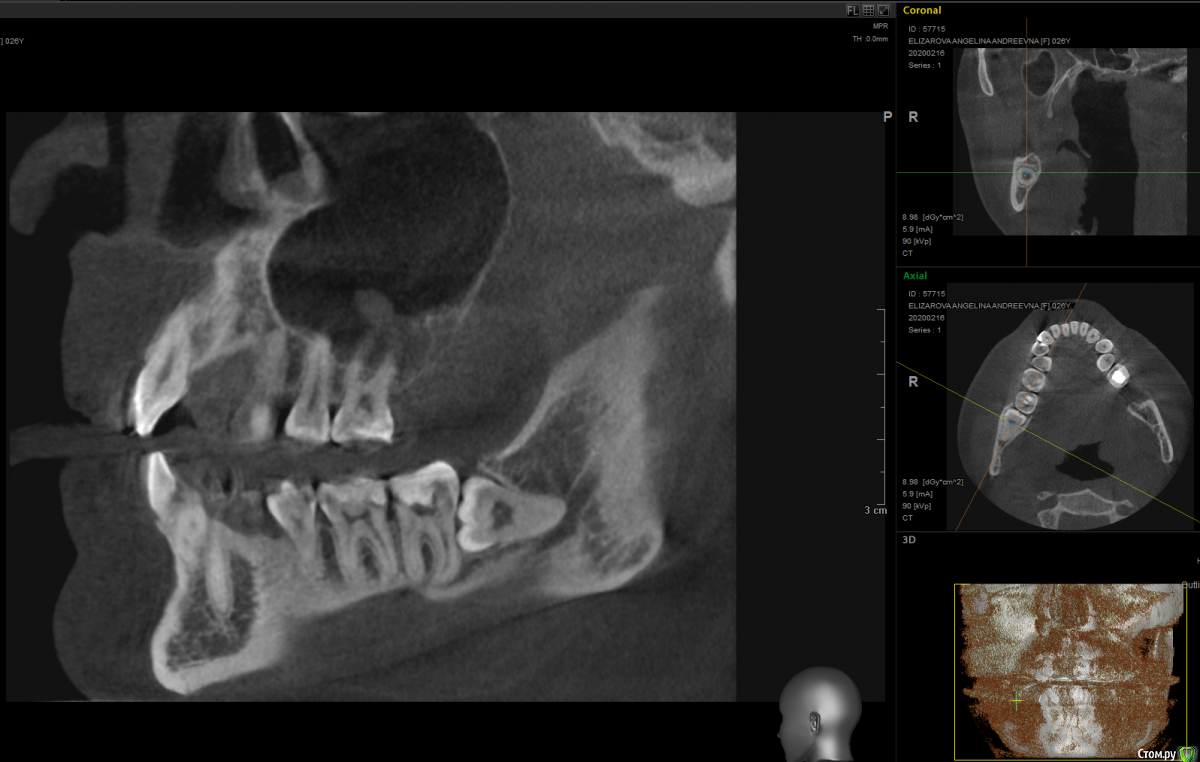

It'sGeorgy Опубликовано 17 февраля, 2020 Поделиться Опубликовано 17 февраля, 2020 Доброго времени суток! Пациентка жалуется на чувство онемения справа в области нижней челюсти. На КТ вот такая картина:Не вижу больших проблем с удалением зуба, но не могу понять есть ли новообразование в челюсти, и, если есть, каковы его размеры:или? Заранее спасибо за помощь. Ссылка на комментарий

Dr.Berger Опубликовано 18 февраля, 2020 Поделиться Опубликовано 18 февраля, 2020 Доброго времени суток! Пациентка жалуется на чувство онемения справа в области нижней челюсти. На КТ вот такая картина:Screenshot_4.pngНе вижу больших проблем с удалением зуба, но не могу понять есть ли новообразование в челюсти, и, если есть, каковы его размеры:восемь1.pngиливосемь2.png? Заранее спасибо за помощь.а что на КТ у 47 зуба? Там периодонтит!? Ссылка на комментарий